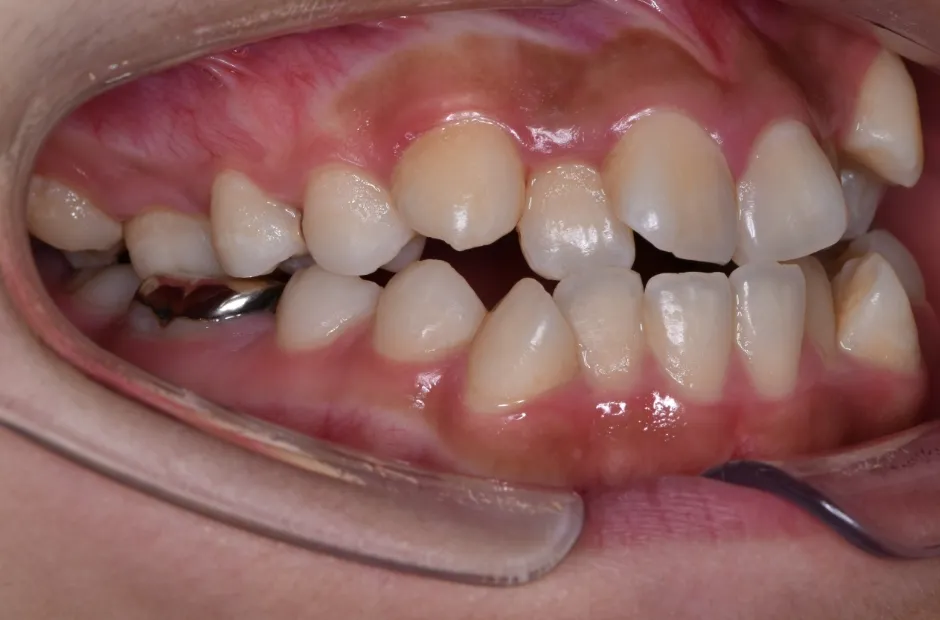

治療症例

ブラケット矯正

前歯部反対咬合

| 診断名・主訴 | 前歯部反対咬合 |

|---|---|

| 年齢・性別 | 14歳・男性 |

| 治療期間・回数 | 1年2か月 |

| 治療に用いた主な装置 | ブラケット矯正 |

| 抜歯部位 | なし |

| 治療費 | 60万円(税抜) |

| リスク・副作用 | 装置による違和感・疼痛・歯肉退縮・歯根吸収・虫歯のリスクなど |

治療前